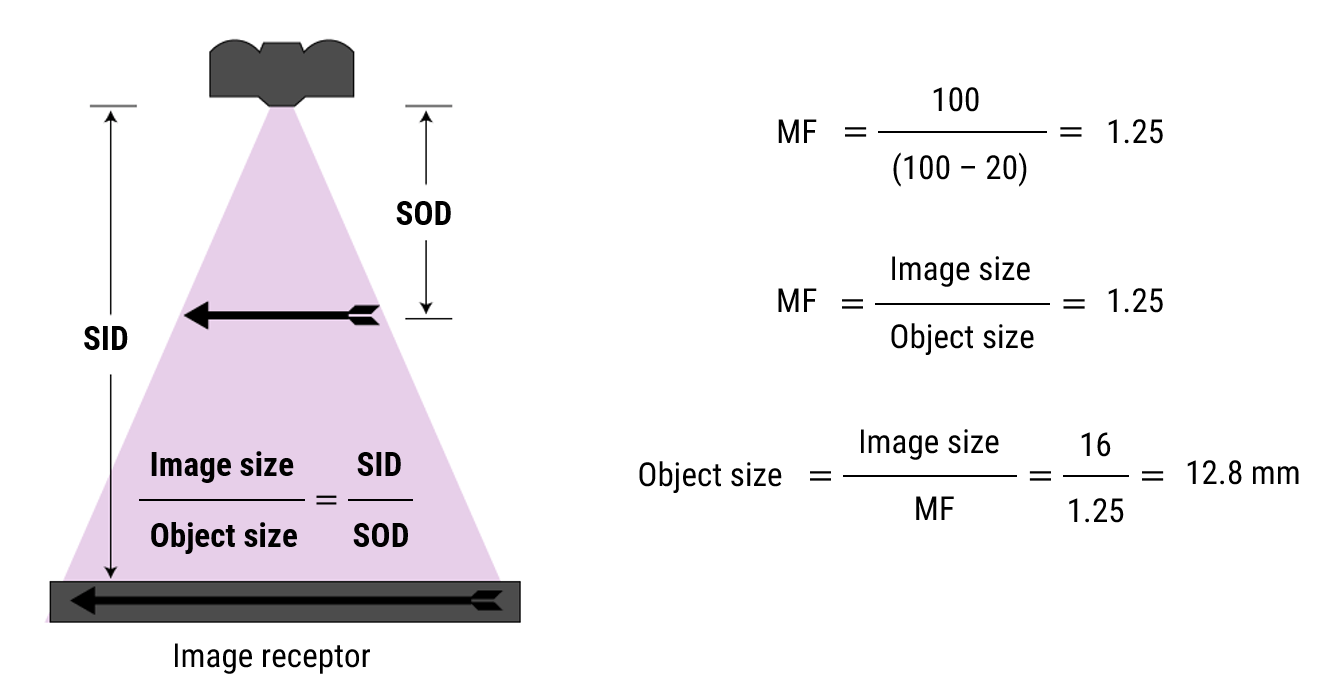

Let’s practice

- SID = 100 cm

- OID = 20 cm

- Image = 16 mm

- Actual size?